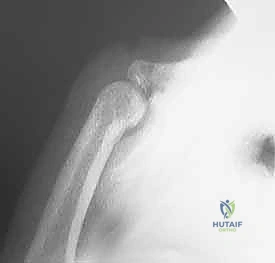

• Standard Radiographs: Obtain high-quality anteroposterior, true lateral, and oblique views of the injured digit only. "Fanned four-finger lateral" views of the entire hand are often inadequate and can miss subtle fracture-dislocations.

• Fluoroscopy: As mentioned, indispensable for dynamic assessment of stability and confirming concentric reduction.

Image

FIG 2A. Disruption of resting flexor cascade. (Note: Image caption from original text was "A. Disruption of resting flexor cascade." but the image itself shows fluoroscopy, so I will align with the visual content.)